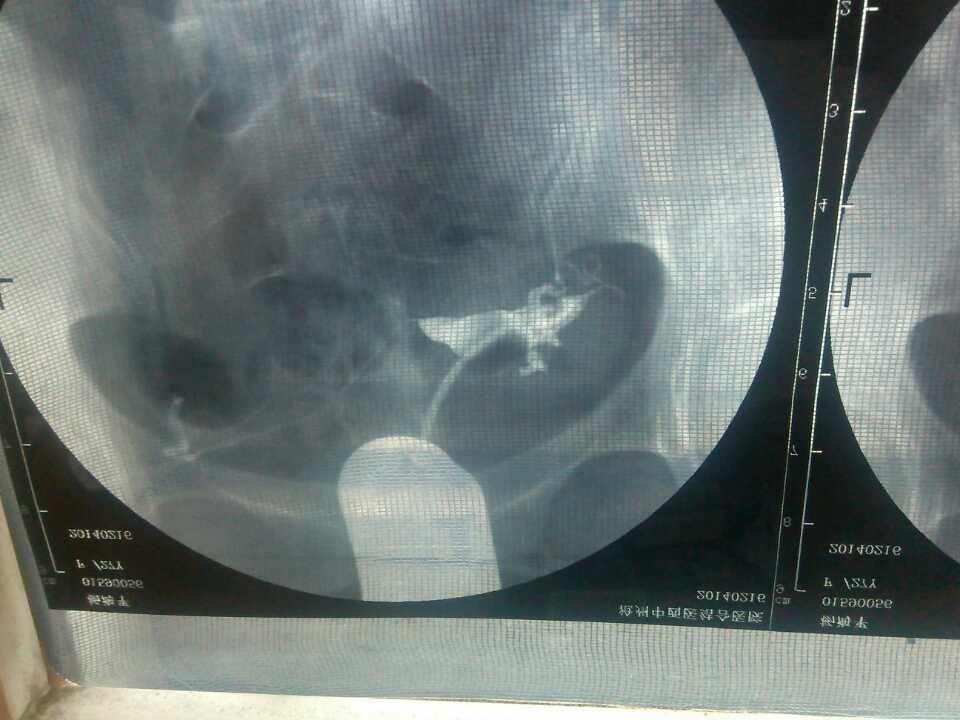

不孕 造影单子帮忙看看 点击展开 匿名用户 2014-04-10 08:51 为您推荐: 其他回答 病情分析: 你好,应该是输卵管堵塞引起的。 指导意见: 可以考虑腹腔镜手术来治疗,术后注意不可过早恢复同房,及时复查。 独水凡_xjeq 2014-04-10 10:34 相关问题 医生你们好帮忙看看我这个造影单子有木有问题 因为我备孕一年 请问医生,不孕单子上这种病情应该怎么办呢?需要手术吗? 谁帮忙看看我下面问题补充里面的检查结果?看看我能不能怀孕??有没有不孕症??